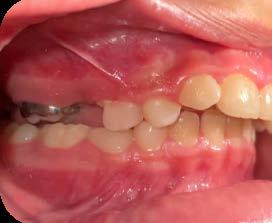

Es por lo anterior, que durante el intercambio dentario, la vigilancia periódica, a través de radiografías, análisis de modelos de estudio y una evaluación clínica, son acciones necesarias para la planeación adecuada de un tratamiento interceptivo, en caso de llegar a ser necesario, para generar los cambios y movimientos a nivel ortopédico y ortodóntico respectivamente y así evitar en lo posible una inclusión canina (Figura 7).

Acciones clínicas para el diagnóstico

En la práctica clínica, al hacer la revisión, uno de los signos clínicos motivo de alerta, correspondería a la falta de movilidad de los caninos deciduos cuando ya es tiempo en el intercambio dental,(caninos superiores 10 años ±9 meses, caninos inferiores 9 años ±9 meses)9 así como señalar si existe la ausencia de los mismos, la falta de espacio en el arco dental para la erupción de los caninos

permanentes, por el que el apoyo radiográfico inicial confirmará la posibilidad de una inclusión canina en proceso (Figura 16).